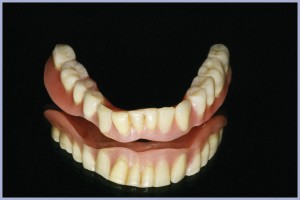

La dima radiologica, privata del repere, permette il montaggio del modello master 3D in articolatore per la realizzazione della protesi provvisoria, un Toronto bridge su sei impianti e relativi monconi per protesi avvitata, con un cantilever a sinistra (Figg. 38-48).

- Figg. 45, 46 – Protesi provvisoria montata in articolatore

- Fig. 46

- Figg. 47, 48 – Protesi avvitata provvisoria posizionata sul modello master 3D

- Fig. 48